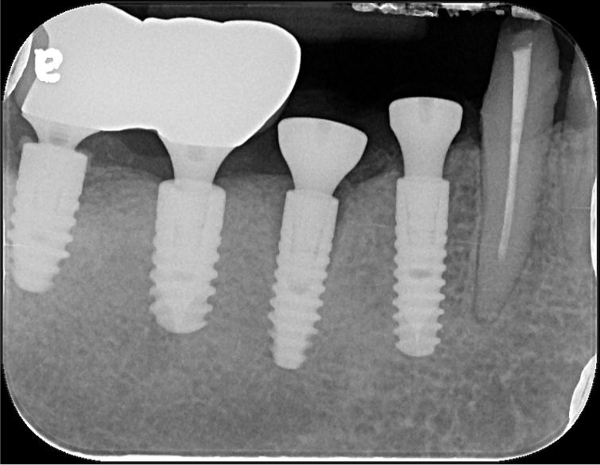

術後X光

治療後X光,穩合度良好